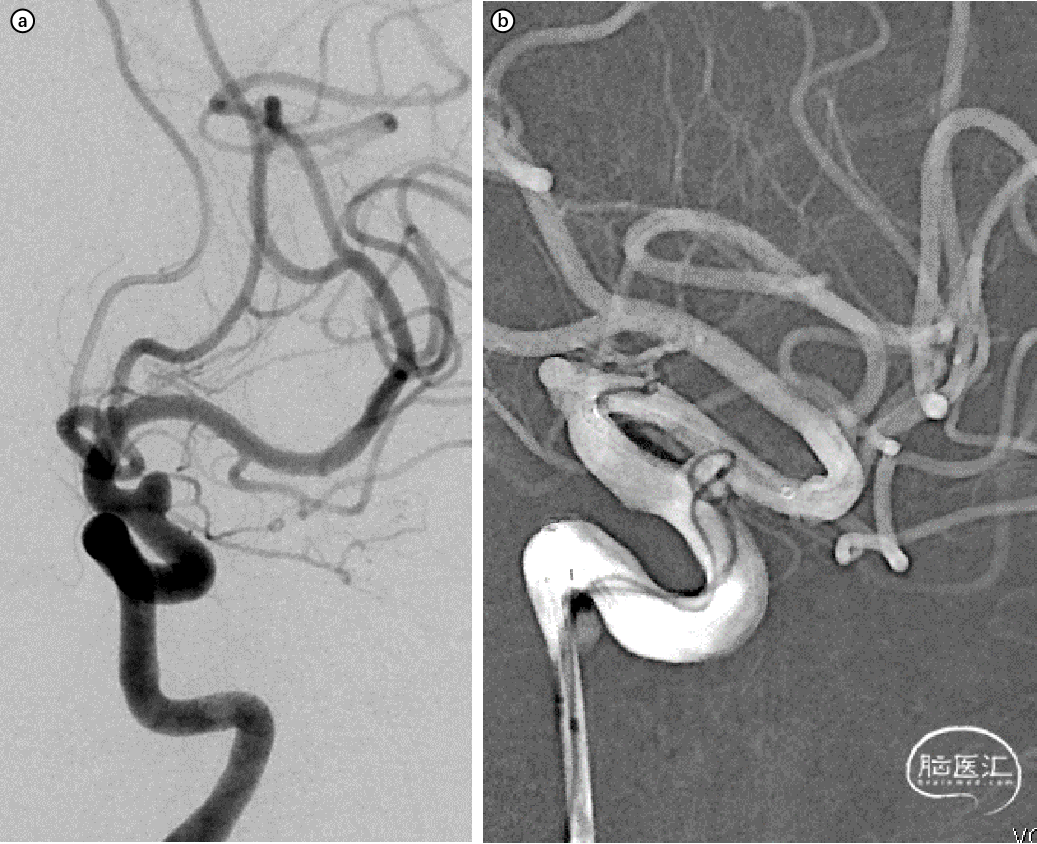

手术过程

图2. a,b:采用支架半释放辅助栓塞宽颈动脉瘤,动脉瘤近端血管弯度较大。

图2. c,d:编织支架(LEO+3.5×25)过弯时卸张力,支架导管沿小弯侧走行,充分打开。